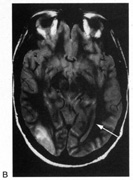

Fig. 18. Magnetic resonance imaging scan of patient with stroke causing a right hemiachromatopsia as well as partial superior quadrantanopia.

Achromatopsia in the contralateral hemifield alone can follow unilateral right or left occipital lesions (Fig. 18). Patients are typically asymptomatic until the defect is demonstrated on examination.234,235 Hemiachromatopsia is usually associated with a superior quadrantanopia;234,235,241 therefore, the color defect is only demonstrable in the remaining inferior quadrant. The preserved color vision in the ipsilateral hemifield allows normal or near-normal performance on centrally viewed tests of color vision such as pseudoisochromatic plates. The incidence of hemiachromatopsia is probably underestimated, given its asymptomatic nature and the failure of routine clinical color tests to detect its presence.